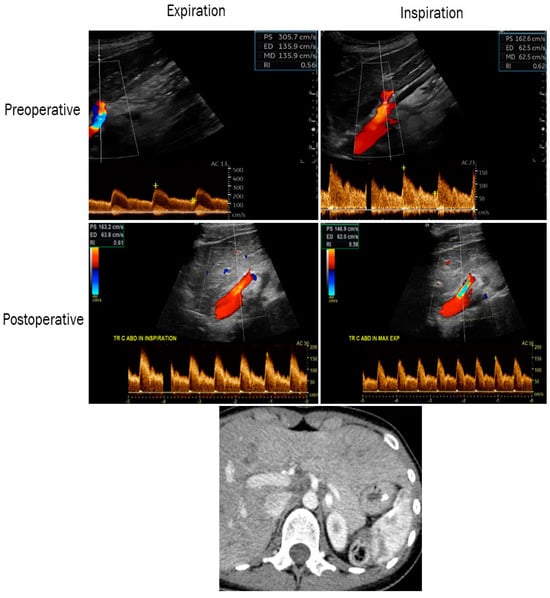

| Patients (n = 7) | |

| Treatment by surgery alone, n (%) | 5 (71.4) |

| Endovascular treatment alone, n (%) | 0 (0) |

| Endovascular and surgical treatment, n (%) | 2 (28.6) |

| Relief of symptoms after treatment, n (%) | 2 (28.6) |

| Time after treatment and last follow-up visit (days), median, (Q1, Q3) | 180 (Q1; 27.5–Q3; 722.5) |

| CA PSV (m/s) after treatment, median, (Q1, Q3) | 1.8 (Q1; 1.5–Q3; 2.4) |

| CA EDV (m/s) after treatment, median, (Q1, Q3) | 0.6 (Q1; 0.5–Q3; 0.8) |